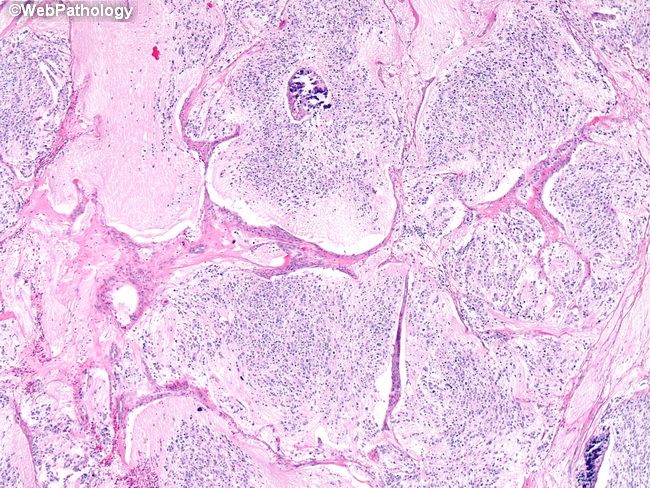

Стадии нейробластомы у детей

Стадии нейробластомы у детей 114 фото